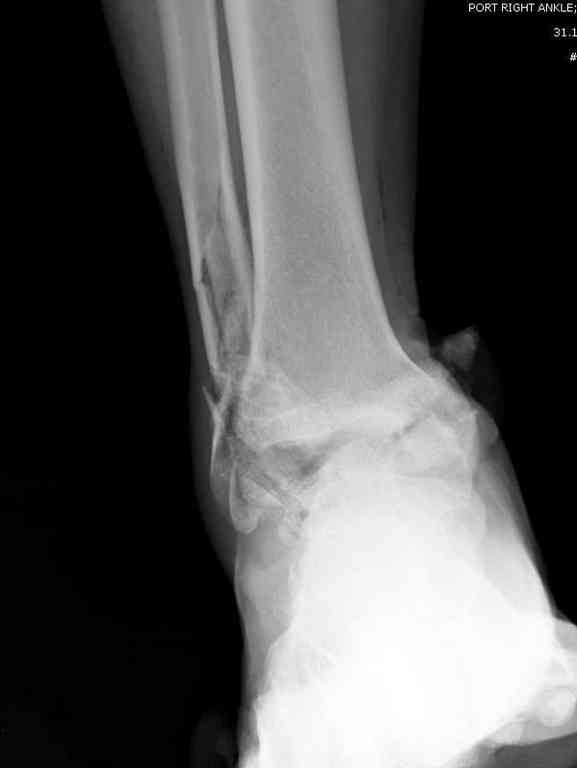

10 дней назад поступил с открытым повреждением медиальной лодыжки и переломо вывихом таранной кости. Ургентно сделана репозиция с наложением наружного фиксатора + Irrigation&Debridment.

Во время репозиции выявили повреждение заднего сухожилия м. тибиалис и задней большеберцовой артерии. Медиальную рану удалось закрыть частично и установлен вакуум.